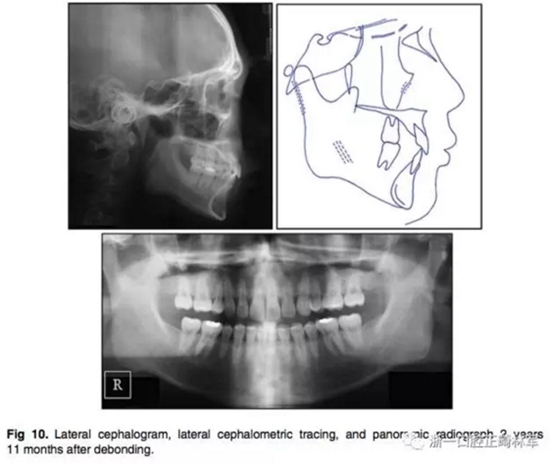

3.在2年11個(gè)月后,患者回來(lái)復(fù)診,他的面部形態(tài)仍然可以接受,但是他的唇部厚度顯著增加,結(jié)果,他的唇部已經(jīng)變得略微突出(Fig 9、Fig10)。他的咬合仍然穩(wěn)定,但他的咬合力略有增加。切牙區(qū)出現(xiàn)了間隙。

4.頭顱測(cè)量疊加顯示有一定的下頜頜骨生長(zhǎng)。矢狀面骨關(guān)系穩(wěn)定(ANB由4.4為4.1°),下頜平面逆時(shí)針旋轉(zhuǎn)(Fig 11)。